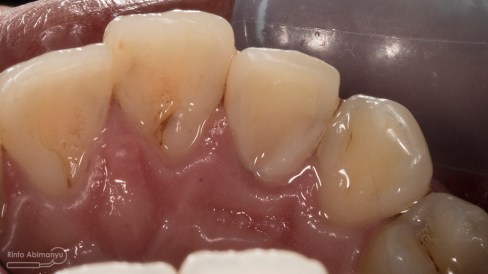

Tentang gigi 12 yang mengalami karies di palatal. Jadi pasien datang mengeluhkan di belakang giginya terasa ada lubang dan sering kemasukan makanan. Gigi tersebut dulu pernah sakit tapi sekarang sudah tidak terasa lagi. Gigi itu belum pernah ditambal sama sekali.

Setelah saya lihat kondisinya seperti ini…